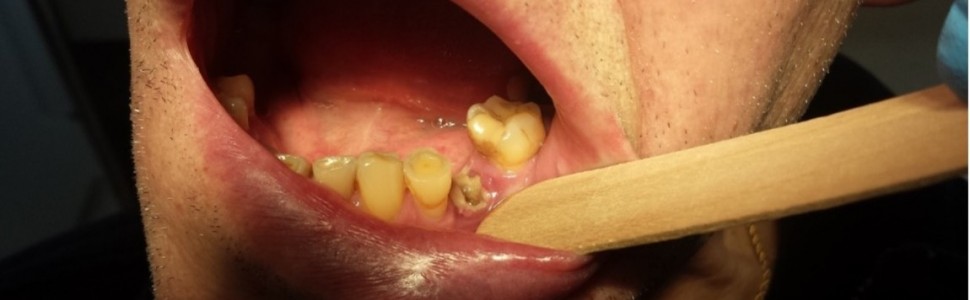

Leki o działaniu antyresorpcyjnym, które są szeroko stosowane w terapii chorób przebiegających ze spadkiem masy kostnej, mogą wpływać niekorzystnie na stan jamy ustnej. Do najpoważniejszych powikłań terapii antyresorpcyjnej zalicza się martwicę kości szczęk związaną ze stosowaniem leków (Medication-Related Osteonecrosis of the Jaw, MRONJ). Obserwowano również występowanie owrzodzeń i nadżerek na błonie śluzowej jamy ustnej, utrudnione gojenie ran po zabiegach chirurgicznych, niekorzystny wpływ na przebieg leczenia ortodontycznego, zaburzenia w rozwoju i wyrzynaniu się zębów u dzieci, istotne zmiany w składzie śliny. Ze względu na stale rosnącą liczbę pacjentów poddanych terapii antyresorpcyjnej istotne jest uświadomienie lekarzy dentystów, jakie mogą być skutki stosowania leków antyresorpcyjnych w odniesieniu do jamy ustnej i związane z tym implikacje kliniczne w trakcie leczenia stomatologicznego.

Antiresorptive drugs are widely used in the treatment of diseases associated with bone loss. Medication-Related Osteonecrosis of the Jaw (MRONJ) is one of the most serious complications of antiresorptive therapy. The occurrence of ulcerations and erosions on the oral mucosa, delayed healing after surgical procedures, adverse effect on the course of orthodontic treatment, disturbances in the development and eruption of teeth in children, and significant changes in the composition of saliva were observed. Due to the constantly growing number of patients undergoing antiresorptive therapy, it is important to make dentists aware of the effects antiresorptive drugs have on the oral cavity, and its related clinical implications during dental treatment.